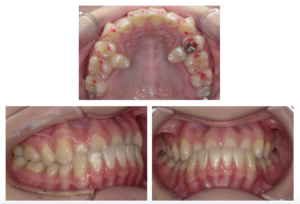

受け口の治療(インビザライン マウスピース矯正)

治療前

| 主訴 | 21歳女性 受け口を治したい |

| 治療期間 | 2年4ヶ月 |

| 治療費 | 82万円+税(抜歯2本の代金10000円と追加アライナー2回分を含む) |

| 治療内容 | インビザラインで矯正治療を行った。上の第二小臼歯は内側に入り込んでいたので、抜歯が必要であった。下顎に隣接面削合(IPR)を行い、下の前歯を内側に引き込むとともに、内側に傾斜している上の前歯を外側(唇側)に傾斜させた。難しいケースだが、患者さんの協力により、順調に経過した。 |

| 治療のリスク | マウスピースを規定の時間使用しないと、予定通りに治療を進めることが困難になり、治療期間が延長する。噛み合わせが深いので、マウスピースのみで改善が困難な場合はインプラントアンカー等の併用が必要になる可能性がある。 |